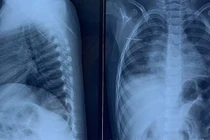

(khoahocdoisong.vn) - Đưa con đến bệnh viện do bị sốt kéo dài, cả gia đình sững sờ được bác sĩ thông báo có một đoạn kim khâu dài 17mm đang nằm trong cơ thể bé.

(khoahocdoisong.vn) - Khoa ngoại tổng hợp - Bệnh viện Nhi trung ương vừa tiếp nhận và phẫu thuật thành công gắp dị vật cho bé P.D.C. (3 tuổi), bị kim đâm xuyên thành ngực.